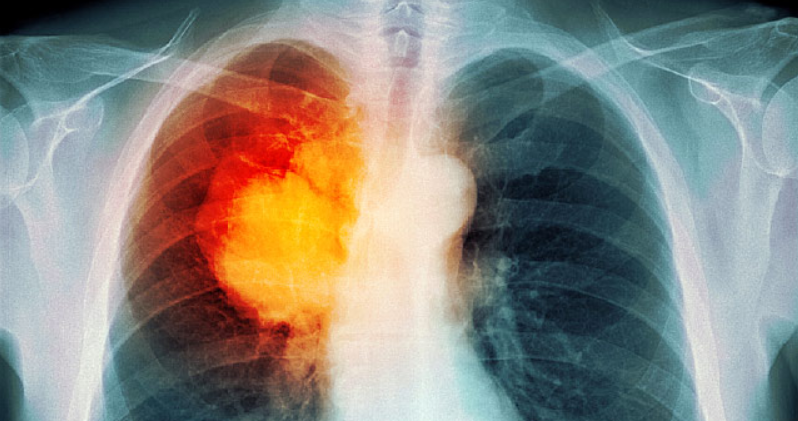

폐암 환자의 허리 통증 치료는 근본 원인에 크게 좌우됩니다. 통증이 종양에 의한 압력과 관련이 있는 경우 수술, 화학 요법 또는 방사선 요법으로 치료할 수 있습니다.

뼈 전이가 있는 경우 방사선 치료와 비스포 스포 네이트 (골다공증 치료에 사용되는) 및 약물 인 데스 모둠(disosumab)으로 알려진 약물을 병용하면 통증이 상당히 완화되고 골반 골을 통한 골절의 위험도 감소합니다.

결국, 폐암과 관련된 심각한 통증에 효과적인 방법이 많이 있습니다. 불행히도, 너무 많은 사람들이 통증 조절에 매달려 노력합니다. 왜냐하면 그들이 중독될까 두려워하거나 약물이 정말로 필요할 때 "덜 효과적이게 될 것이기 때문이다." 이 두 가지 두려움은 마약을 처방대로 복용하면 근거가 없습니다.

연구 결과에 따르면 증상 발현과 폐암 진단 사이의 시간은 약 12 개월입니다. 때로는 증상을 인식하지 못하거나 적극적으로 무시할 수 있기 때문에 종종 사라질 수 있기를 바랍니다. 허리 통증에 관해서는 특히 그렇습니다. 많은 경우 고려해야 할 것은 우리가 다루어야 할 삶의 사실입니다.

그러나 허리 통증이 당신에게 의미가 없거나 더 심해지고 전형적인 치료법에 반응하지 않는다면 그것을 참아 내지 마세요. 의사를 만나고 발생한 다른 증상에 대해 의논하십시오. 암인 경우 조기 진단으로 조기 치료가 가능하여 완전한 치료 가능성을 높입니다.